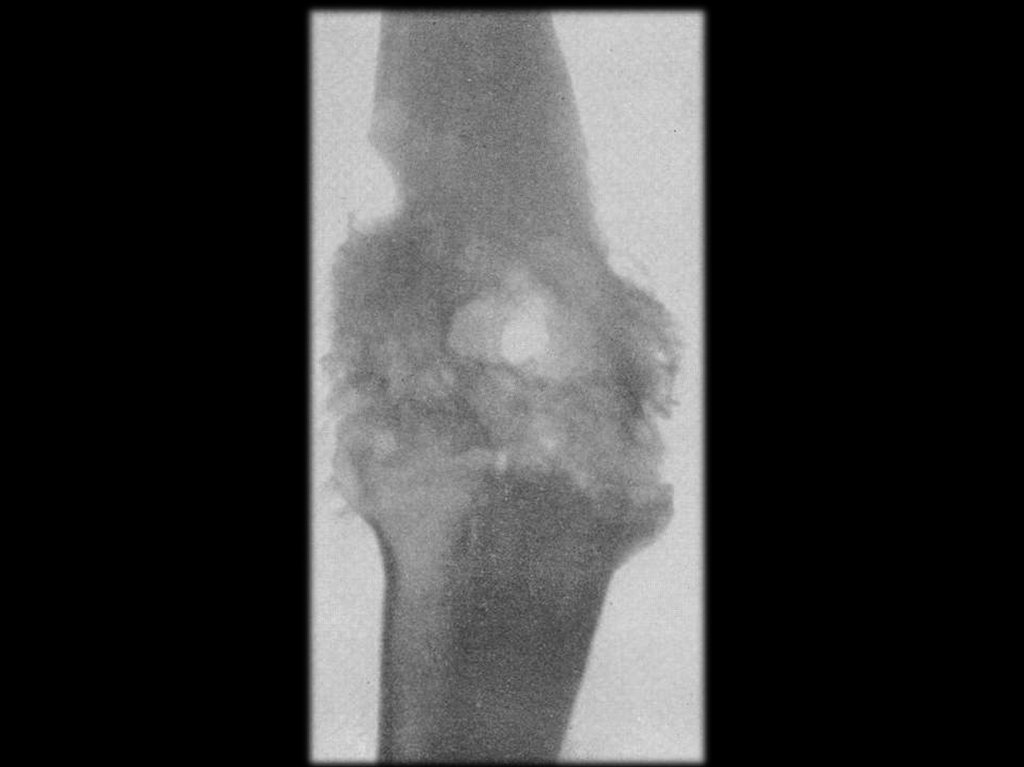

Динамика рентгенологических изменений в

области суставов при хроническом сифилисе

Сифилитический артрит левого коленного

сустава, контрактура